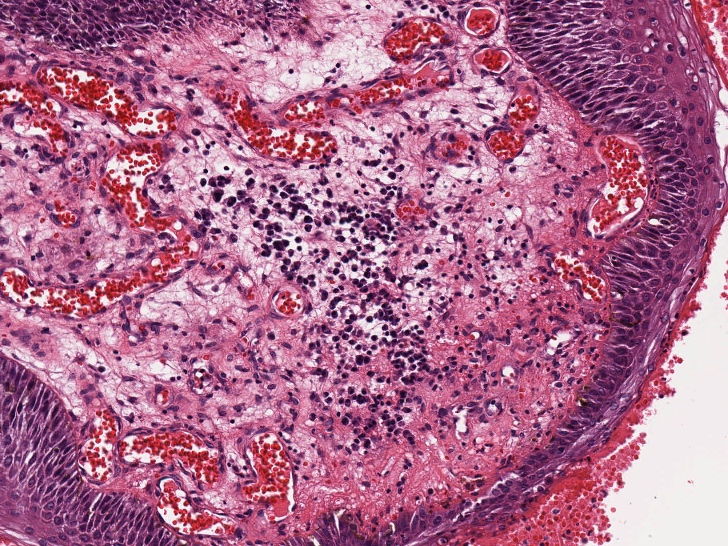

Microscopic (histologic) description

- Resembles condyloma acuminatum

- Diagnostic criteria

- Well formed papillae with a prominent central fibrovascular core

- Hyperkeratosis with parakeratosis and marked acanthosis

- Koilocytes on upper third of the squamous epithelium

- Chronic inflammatory infiltration

- Local extension and displacement of surrounding tissues but no evidence of dysplasia / invasion (WHO Classification of Tumours Editorial Board: Digestive System Tumours, 5th Edition, 2019)

- Low mitotic rate, usually confined to the basal layer with no abnormal mitoses (Histopathology 2017;70:938)

- About 30 - 35% may develop an invasive component; especially in high risk HPV positive cases (Virchows Arch 2020;476:543, Dis Colon Rectum 1989;32:481)

Microscopic (histologic) images